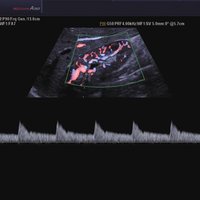

• Farb-Doppler

• Pulsed Wave (PW)-Spektral-Doppler

• Continuous Wave (CW)-Doppler

• Power-Doppler (PD)

• Directional Power Doppler (DPD)

• Color Opt Flow™ bietet kraftvollere Farben und verbessert die Bildqualität.